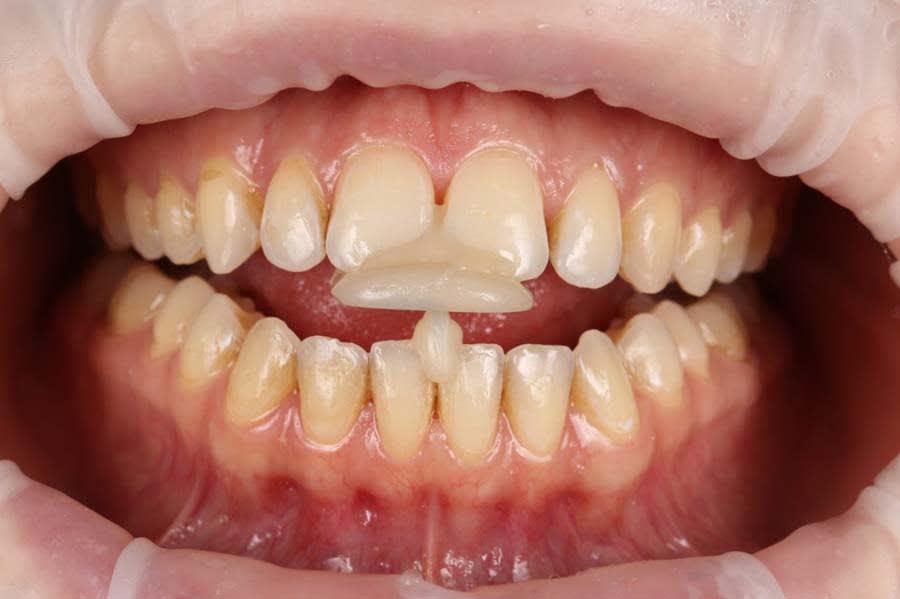

A 26-year-old female patient presented with complaints of unsatisfactory smile esthetics, difficulty biting food, and speech issues. Her medical history was unremarkable. Clinical examination revealed an anterior open bite, mild chronic generalized periodontitis, and impacted third molars in the third and fourth quadrants. Accurate diagnosis of occlusal issues was critical in the treatment planning.5

A panoramic radiograph was recorded (Figure 1), followed by a clinical examination (Figure 2). A jig was fabricated to stabilize centric relation (CR) (Figure 3), and jaw movements were analyzed using a virtual articulator in CAD software (exocad, exocad.com) (Figure 4). Digital wax-ups and guides were employed to enhance surgical and restorative accuracy.6